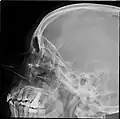

![]() Lateral projection of the paranasal sinuses | |

Paranasal sinuses radiograph (lateral)